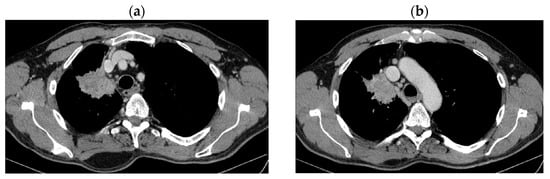

2. Case Presentation

2.2. Monitoring 2022: Oncological Commission 1910/16.08.2022

2.3. Oncological Committee 07/25/2023 Recommended

- Consider rescue re-irradiation (SBRT), taking into account the current primary tumor dimensions of 24 × 34.2 mm on PET CT from 06/2023 and also the total dose previously administered (08–09/2020), the previously applied fractionation, the time between the two irradiations, the cellular repair time and the dose constraints for the organs at risk.

| DOWNSTAGING from metastatic to locoregional stage | From cT3N3M1b(OSS) stage IVA | In cT2bN3M0, stage IIIB (without M1OSS) |